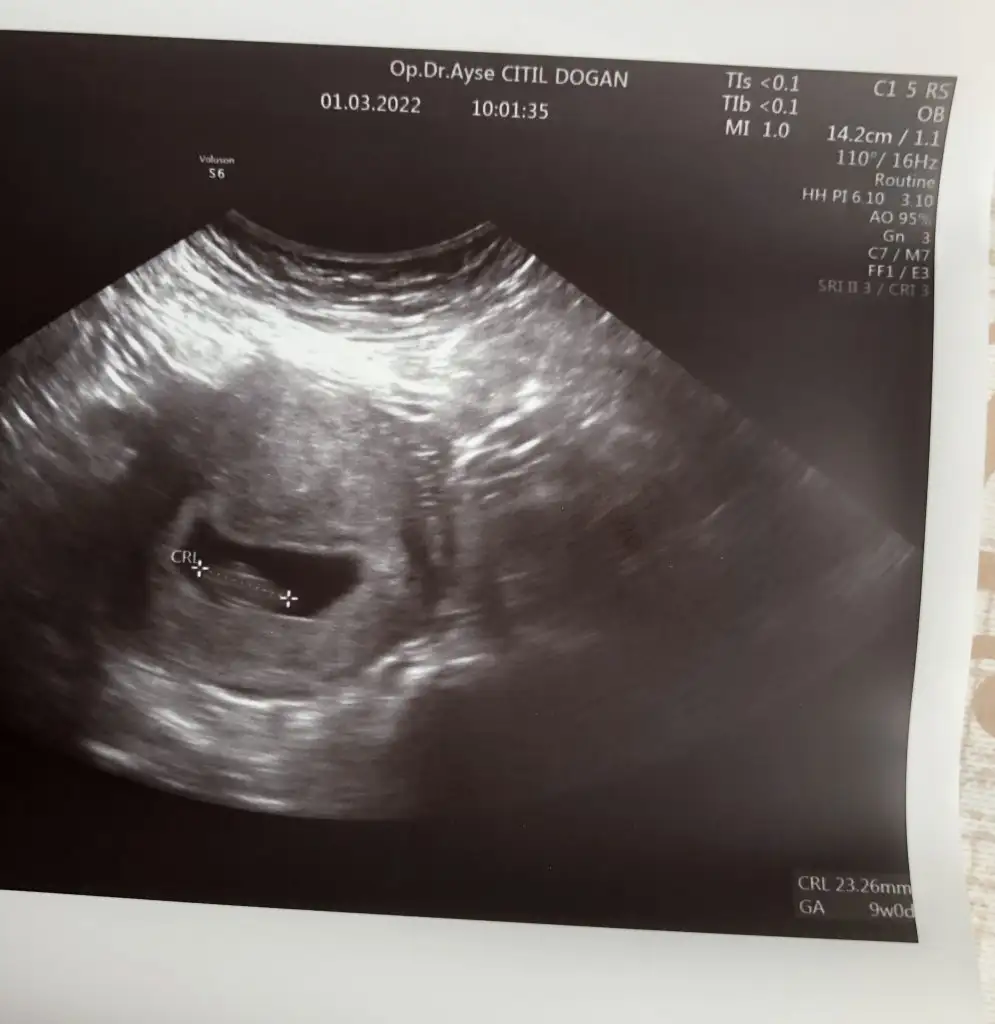

Arkadaşlar bugün doktora gittim. Karından ultrason baktı. 8+5 olmuş. Şükürler olsun iyi göründü. Korkuyorum diğer kaybımdan dolayı sağlıkla devam eder inş

uştrasonuna bakar mısınız? Cinsiyeti nedir

sizce?